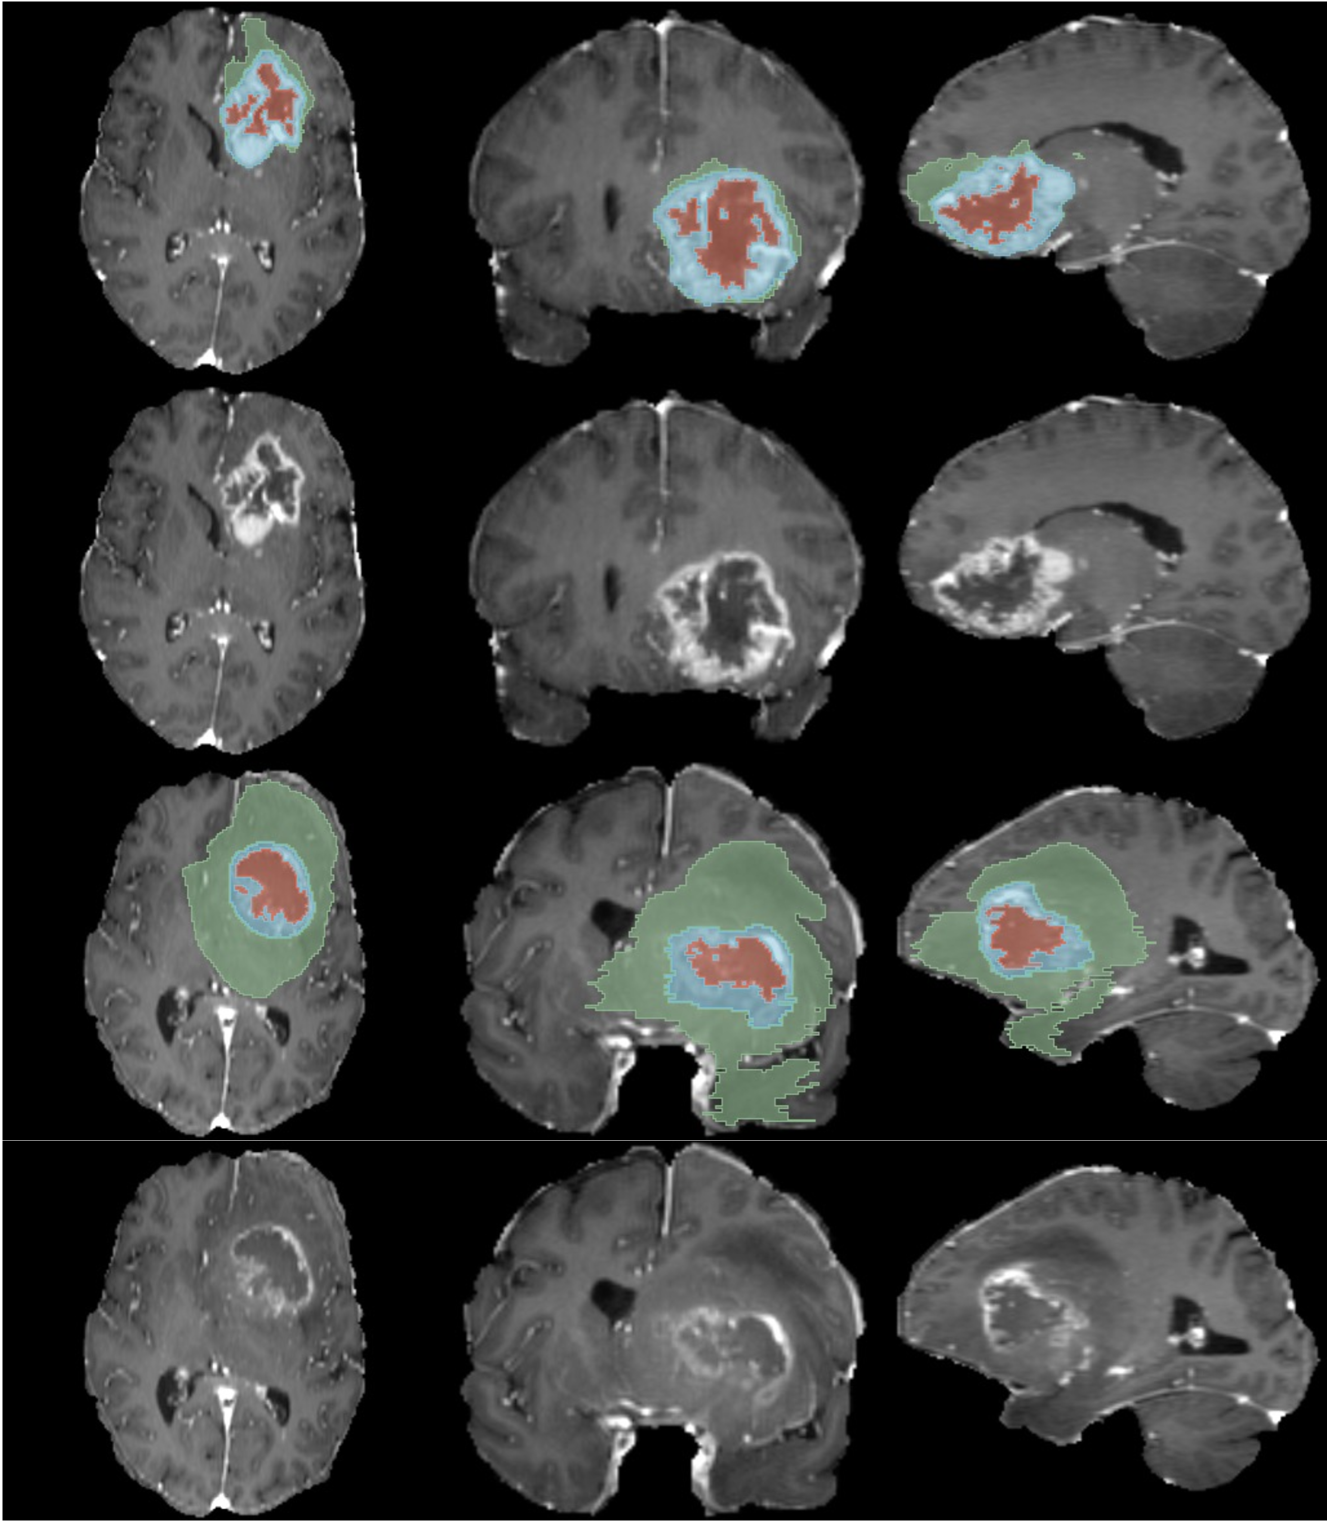

In G (Figures 17, 18, 19 and 20) and H (Figures 21, 22 and 23) are presented CT and MRI synthetic cases with the respective tumor segmentations.

The segmentation of brain tumors on MRI scans using synthetic cases yielded competitive results compared to using real cases. This task is less challenging than the segmentation of tumors on H&N CT scans, as evidenced by the high DSC of 0.89 achieved by the model trained on real data, as well as the MS-SSIM value of 0.7201, which indicates that the MRI dataset is less variable, making it easier for the generative models to learn the real distribution. Nevertheless, the high DSC achieved by the best model trained on synthetic cases suggests that the synthetic cases exhibit higher fidelity to the real cases, which is supported by the CCC shown in Fig. 4. The segmentation models trained on synthetic data generated by GANs yielded worse results compared to those trained on synthetic data produced by DDPMs. The MS-SSIM of 0.8551 shows that GANs were not able to reproduce the variability of the original MRI dataset. The WT, composed by the ET, NCR and ED, shows the greatest difference between real and synthetic data. This was expectable as the ED contains a hyperintense signal in the FLAIR modality and is more difficult to recognize on the used T1c scans. With a lower contrast difference between the ED and the surrounding tissue, the generative networks had greater difficulty generating this region with higher fidelity, leading to poorer segmentation results. Some synthetic examples can be seen in H. It is also important to notice that the sampling methods ‘DPM++ 2M’ and ‘DPM++ 2M SDE’ show consistently better results than the other methods for all three models. A narrower distribution of cases and a higher similarity between real and synthetic MRI scans recognizable by the high MS-SSIM and low MAE, respectively, are among the main reasons why the generative models were able to better learn the distribution of the MRI data.